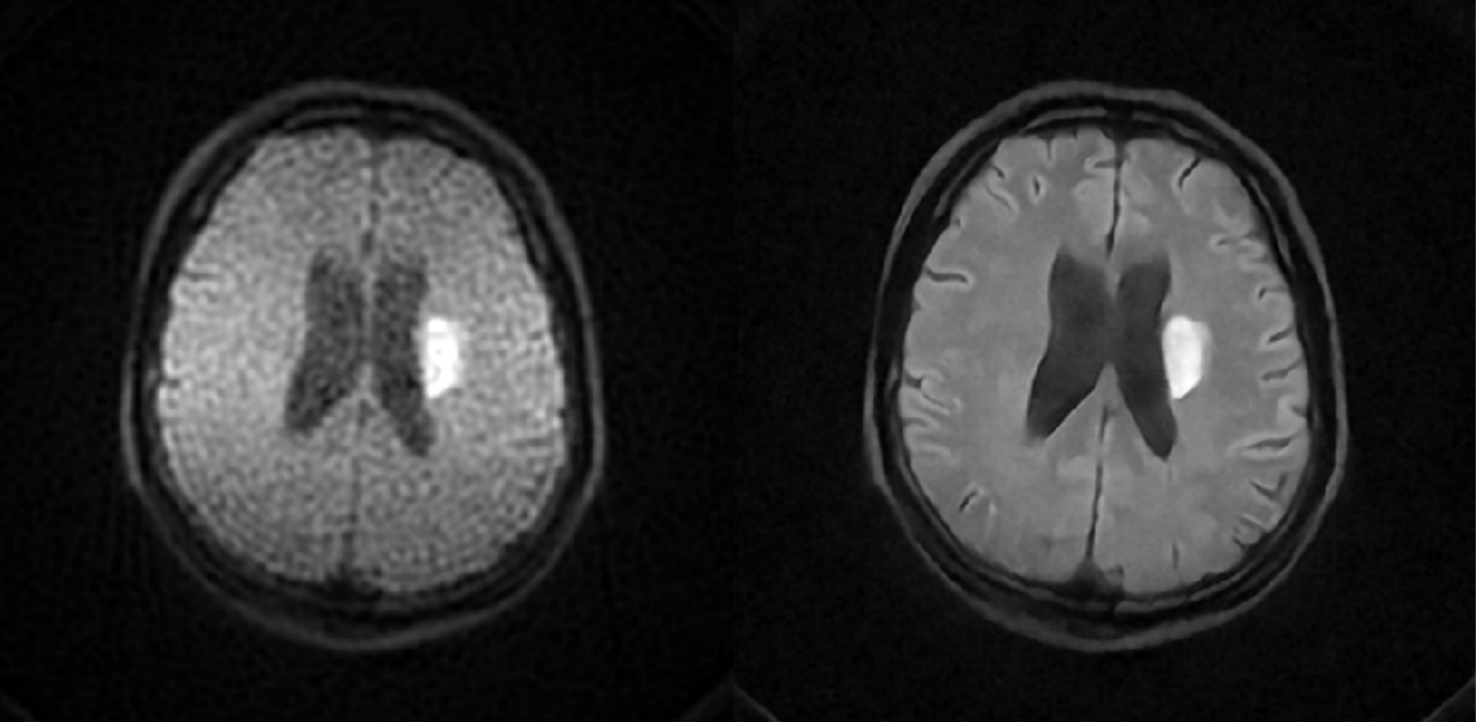

Left: the PMRI image as input; Right: the SynthMRI image as output